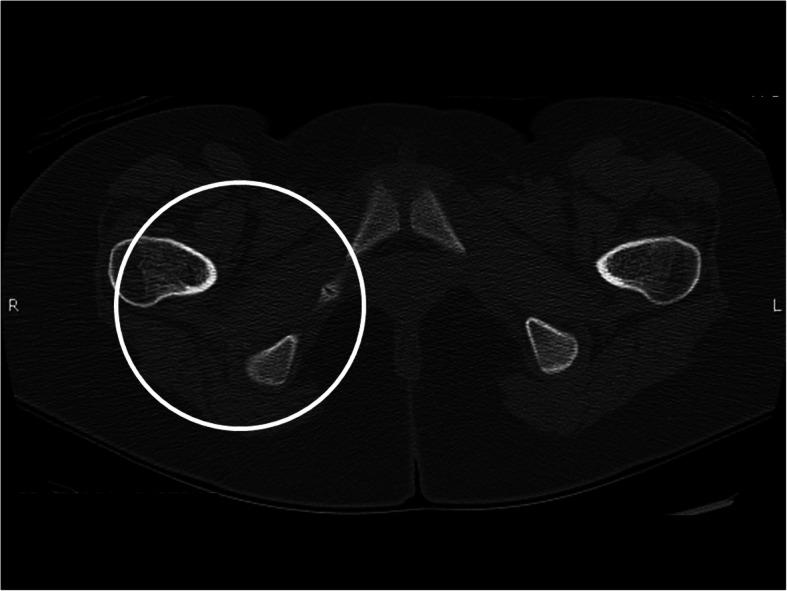

We describe the case of a 13 year-old girl with overlap syndrome with features of juvenile dermatomyositis and systemic lupus erythematosus. After 22 months of extensive immunosuppressive therapy, including monthly IVIG and Rituximab, she continued to have pain and weakness of the lower extremities. A CT scan was performed which showed significant multifocal soft tissue calcifications of the pelvis. She was started on treatment with oral alendronate with the goal of improving her calcinosis and improving her symptoms. After several months of therapy, our patient reported subjective improvement of her lower extremity pain and weakness, as well as complete resolution of abnormalities previously seen on physical examination. A repeat CT scan of the pelvis was performed after 11 months of therapy and demonstrated complete resolution of the previously seen calcinosis.

We report the successful treatment of soft tissue calcinosis with oral bisphosphonates in a patient with juvenile dermatomyositis-systemic lupus erythematosus overlap syndrome. These results provide further evidence that bisphosphonates can be used successfully to treat calcinosis cutis in pediatric rheumatologic disorders. Additionally, the results provide new evidence that they can be used specifically in juvenile dermatomyositis-systemic lupus erythematosus overlap syndrome, which has not been previously reported.

我们描述了一名13岁女孩的病例,她患有重叠综合征,具有幼年皮肌炎和系统性红斑狼疮的特征。在进行了22个月的广泛免疫抑制治疗后,包括每月静脉注射免疫球蛋白和利妥昔单抗,她的下肢仍持续疼痛和无力。进行了CT扫描,结果显示骨盆有明显的多灶性软组织钙化。她开始接受口服阿仑膦酸钠治疗,目的是改善她的皮肤钙化并缓解症状。经过几个月的治疗,我们的患者报告下肢疼痛和无力主观上有所改善,并且之前体格检查中发现的异常完全消失。治疗11个月后对骨盆进行了重复CT扫描,结果显示之前所见的皮肤钙化完全消失。

我们报告了口服双膦酸盐成功治疗一名患有幼年皮肌炎 - 系统性红斑狼疮重叠综合征患者的软组织钙化。这些结果进一步证明双膦酸盐可成功用于治疗小儿风湿性疾病中的皮肤钙化。此外,这些结果提供了新的证据,表明它们可专门用于幼年皮肌炎 - 系统性红斑狼疮重叠综合征,此前尚无相关报道。